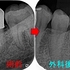

口腔内

2026 EEdental YOA (2).jpg

痛みがあった為か、咬合調整を行い咬み合わせを下げているみたいです。